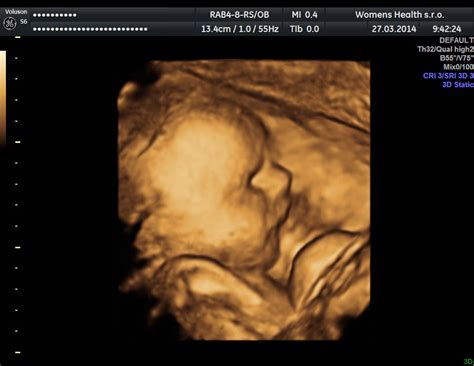

3D ultrazvuk zobrazuje síce priestorový, ale iba statický (nepohyblivý) obraz plodu. 4D ultrazvuk je o úroveň vyššie, čiže zobrazovanie plodu je v “štyroch” dimenziách, tzn. 3D ultrazvukové zobrazenie plodu, ale nie statické, ale pohyblivé zobrazenie v čase. Pri 3D ultrazvuku vytvoríme obrázok skutočného vzhľadu Vášho bábätka a pri 4D ultrazvuku naviac uvidíte ako sa v danom okamihu bábätko pohybuje. To ako dobre bude možnosť si prehliadnuť bábätko záleží vždy od jeho spolupráce a od množstva plodovej vody.

3D/4D ultrazvuk je moderné vyšetrenie, ktoré pomocou špeciálnej ultrazvukovej technológie zobrazuje dieťatko v brušku mamičky v trojrozmernom obraze (3D) a dokonca aj v reálnom čase pri pohybe (4D). Umožňuje detailnejšie zobraziť tváričku, končatiny či pohyby plodu, čo býva pre rodičov silný emocionálny zážitok. Z lekárskeho hľadiska pomáha lepšie posúdiť niektoré vývojové znaky alebo odchýlky, čo môže prispieť k včasnej diagnostike. Toto vyšetrenie prebieha úplne bezpečne a bezbolestne. Nenahrádza však štandardné skríningové ultrazvuky, ale ich dopĺňa.

Vďaka 3D ultrazvuku budeš mať fotografiu bábätka, najčastejšie sa zobrazuje jeho tvárička, ktorá už na začiatku tretieho trimestra má presne tie tvárové črty, aké bude mať bábätko aj po narodení. Na 4D ultrazvuku môžeš pozorovať bábätko v reálnom čase a pozerať sa, ako sa práve pohybuje, mračí, usmieva alebo hýbe ručičkami. Domov si odnesieš video záznam na USB kľúči.